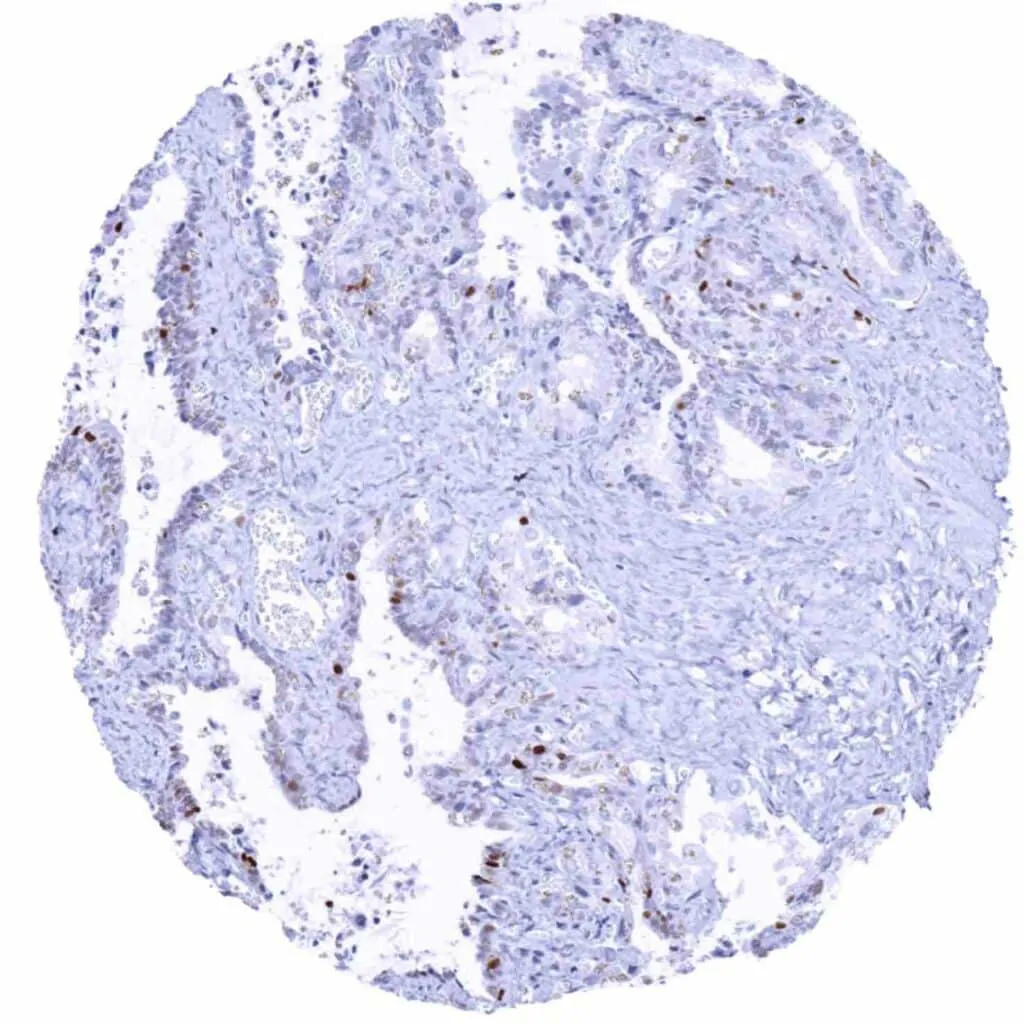

Rectum, mucosa – The strongest MCM2 staining occurs in the deepest epithelial cells of the crypts